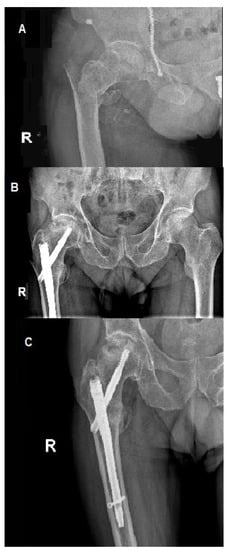

Figure 1 and Figure 2 present AVN of the femoral head developed after surgical stabilization of an intertrochanteric fracture of the femoral bone.

Figure 2. Posteroanterior view of internal fixation of left femoral neck fracture using the dynamic hip screw. (A) Posteroanterior view directly after the procedure; (B) posteroanterior view during control 15 weeks after the procedure, prominent necrosis of left femoral head.